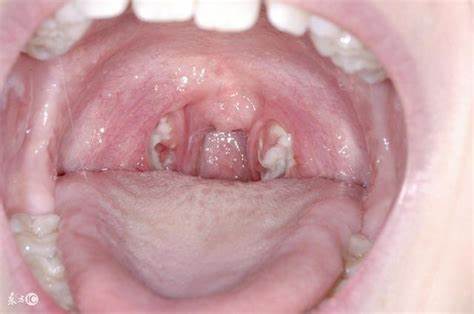

편도결석은 편도선에 박힌 음식 찌꺼기, 세균, 백혈구 등이 굳어져 생기는 작은 입자입니다. 이러한 결석은 주로 입 냄새의 원인이 되며, 때로는 삼키거나 말할 때 불편함을 유발할 수 있습니다.

편도선은 구강 내에 위치하며, 면역 체계의 일부로 작용하여 세균이나 바이러스 등 유해한 요소들을 걸러냅니다. 그 과정에서 입안에 섭취한 음식물 잔여물이 편도선의 작은 틈이나 홈에 끼게 될 수 있습니다. 이곳에 세균이 번식하면서 음식물 잔여물과 함께 굳어지게 되고, 이것이 바로 편도결석을 형성하는 주된 과정입니다. 이러한 결석은 대체로 황백색을 띠며, 작은 크기로 존재합니다.